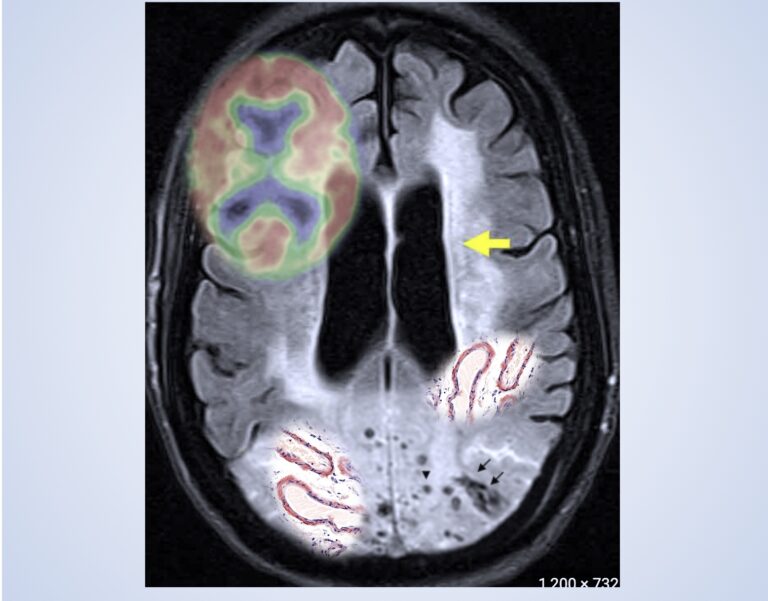

MRI上看到的白質高訊號病灶(White Matter Hyperintensities,WMH)在阿茲海默病人普遍存在,但目前不清楚它是由阿茲海默病變的一部分,還是與系統性血管風險(systemic vascular risk) 因子有關。

• 結果顯示,WMH體積的增加更可能與阿茲海默症的病變過程,如灰質體積減少和腦實質及血管類澱粉沉積有關,而不是與系統性血管風險因子有關。

• 長期追蹤發現,大腦腦葉有微出血(lobar microbleeds)者WMH體積增加更快。

• 阿茲海默患者的WMH增加與灰質萎縮、大腦實質和血管類澱粉沉積有關,但不與較高的系統性血管風險相關。

• WMH較多者,後續追蹤時出現新的lobar CMBs的 機率較高,可能代表較早期的大腦實質和血管類澱粉沈積,先在白質產生變化,在比較後期才出現lobar CMBs

• WMH與類澱粉沉積和腦類澱粉血管病變 (cerebral amyloid angiopathy, CAA)的可能關聯:近期研究表明,WMH可能與澱粉沈積和腦澱粉血管病變(CAA)有關。

• Amyloid PET陽性和WMH體積相關。

• Amyloid PET陽性和WMH體積長期增加相關。

• 具有CMB者在橫斷面和縱向研究中均顯示出較多的WMH體積和長期增加。

• 具有1個CMB與WMH無關,但具有2個或更多已識別的CMB(可能的CAA)與WMH有關。

• 在控制了年齡和灰質體積後,基線時WMH體積高於中位數者在長期追蹤時CMBs的風險較高(OR=2.63;95% CI為1.72-4.03;P < .001)。

• 阿茲海默病患者白質變化與阿茲海默相關病變更相關: 無論在遺傳型和散發型的阿茲海默症中,都顯示出白質高信號變化更可能與類澱粉沈積和神經退化過程(灰質體積)相關。

• CMBs與WMH的關聯: 存在CMBs者其WMH的長期增加明顯高於無CMBs的患者。

• WMH作為生物標記的潛在價值:此研究結果支持將白質損傷做阿茲海默和類澱粉腦血管病變研究的生物標記。